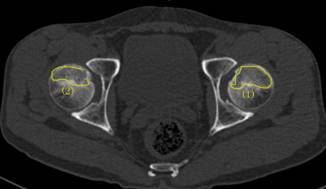

术前报告显示患者双侧股骨头坏死